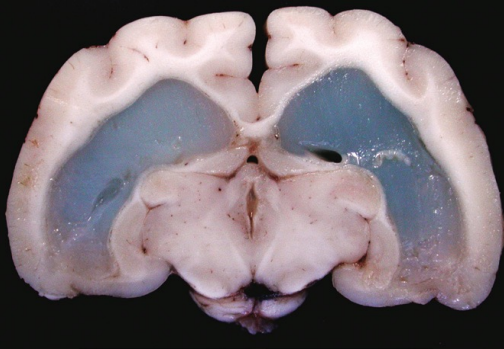

Is the fluid accumulating in the brain ventricles exudate or transudate?

exudate